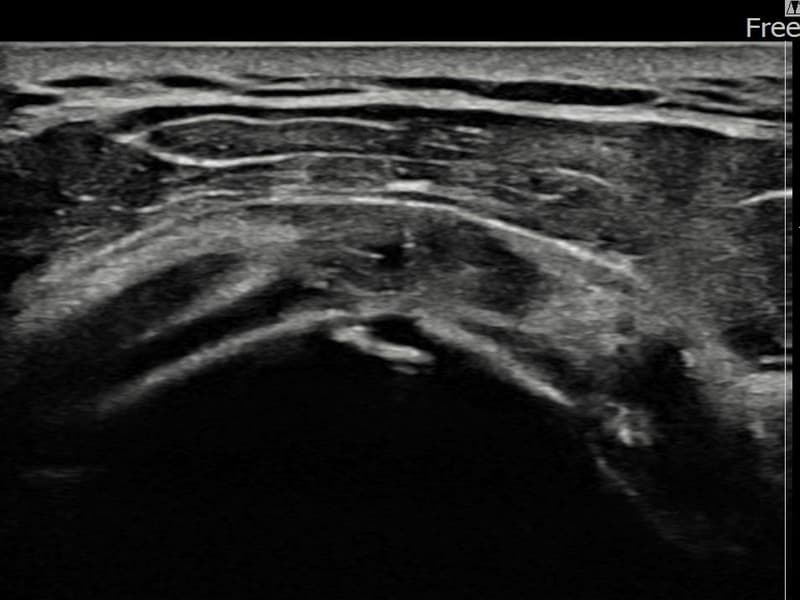

术后

术前超声确认左侧 冈上肌腱 关节面侧部分撕裂,左侧冈上肌腱回声不连续伴肌腱缺损(8mm × 3mm (肌腱厚度约33%缺损))。术后超声显示撕裂部位充满再生组织,肌腱连续性恢复,回声模式正常化。